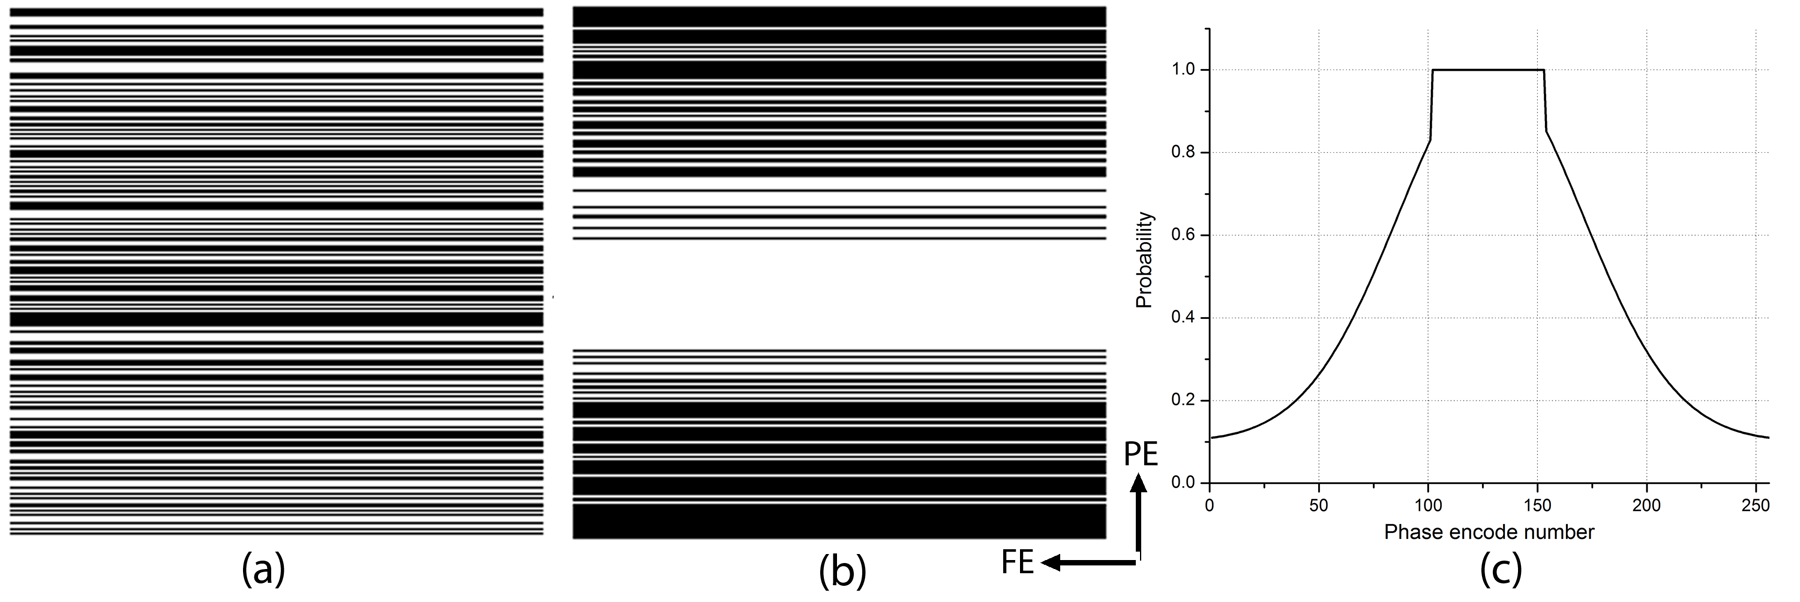

Based on the above property of noiselet transform, we propose to under-sample the noiselet encoded data along the phase encoding direction according to the uniform probability distribution function. One sampling mask using this scheme is shown in Fig. 3(a) where the white lines represent the sampled data points and the black lines represent the unsampled data points. Fig. 3(b) shows the sampling mask for Fourier encoding scheme drawn from a variable density probability distribution function shown in Fig. 3(c).

Fourier encoded CS-MRI A Fourier transform of the image was taken in the PE direction to simulate Fourier encoding. Two types of sampling strategies were used to sample Fourier encoded data: (i) a variable density random sampling pattern as shown in Fig. 3 (a) where samples were taken in the PE direction according to a Gaussian distribution function, and (ii) a completely random sampling pattern as shown in Fig. 3 (b) where samples were taken in the PE direction according to the uniform density function. The non-linear program of (10) was solved to reconstruct the final image for acceleration factors of 2 and 3. In these cases the encoding matrix does not have any sensitivity information (i.e. ).

Noiselet encoded CS-MRI A noiselet transform of the image was taken in the PE direction to simulate noiselet encoding. A completely random sampling pattern was used to sample the noiselet encoded data in the PE direction and the non-linear program of (10) was solved to reconstruct the final image for acceleration factors of 2 and 3. In these cases the encoding matrix does not have any sensitivity information (i.e. ).

Fourier encoded MCS-MRI The reference brain image was multiplied by the sensitivity function to generate eight sensitivity encoded images. The Fourier transform of each these images was taken in the PE direction; only a few PEs were taken according to the Gaussian probability distribution function. MCS-MRI reconstruction of (10) was solved using the nonlinear conjugate gradient on this data. An example sampling scheme for the Fourier encoded MCS-MRI is shown in Fig. 3(a). Noiselet encoded MCS-MRI A Noiselet transform of the sensitivity encoded images was taken in the PE direction, with only a few PE selected according to the uniform probability distribution function. MCS-MRI reconstruction of (10) was solved using the nonlinear conjugate gradient on this data. An example of the sampling scheme for noiselet encoded MCS-MRI is shown in Fig. 3(b).